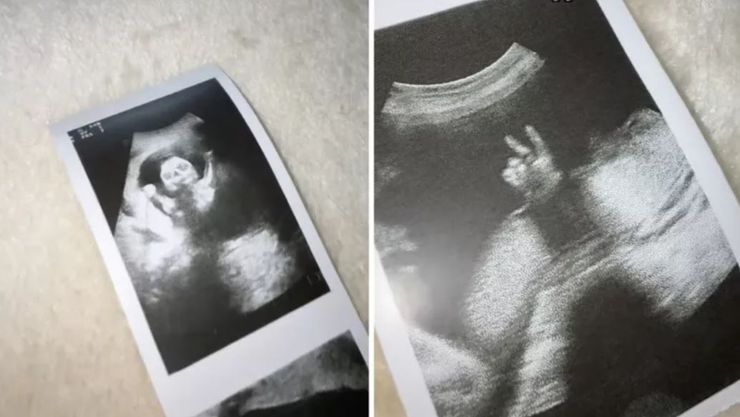

На 22-й неделе беременности Лора надеялась увидеть свою дочь на мониторе, однако полученные кадры стали для нее полной неожиданностью. Ребенок на ультразвуковом исследовании имел выпученные глаза и широкую улыбку, что создавало жуткий эффект. На одной из фотографий малышка будто подняла руки, а на другой — складывала пальцы в знак победы.

На одной из фотографий малыш будто поднял руки, а на другой — складывал пальцы в знак победы